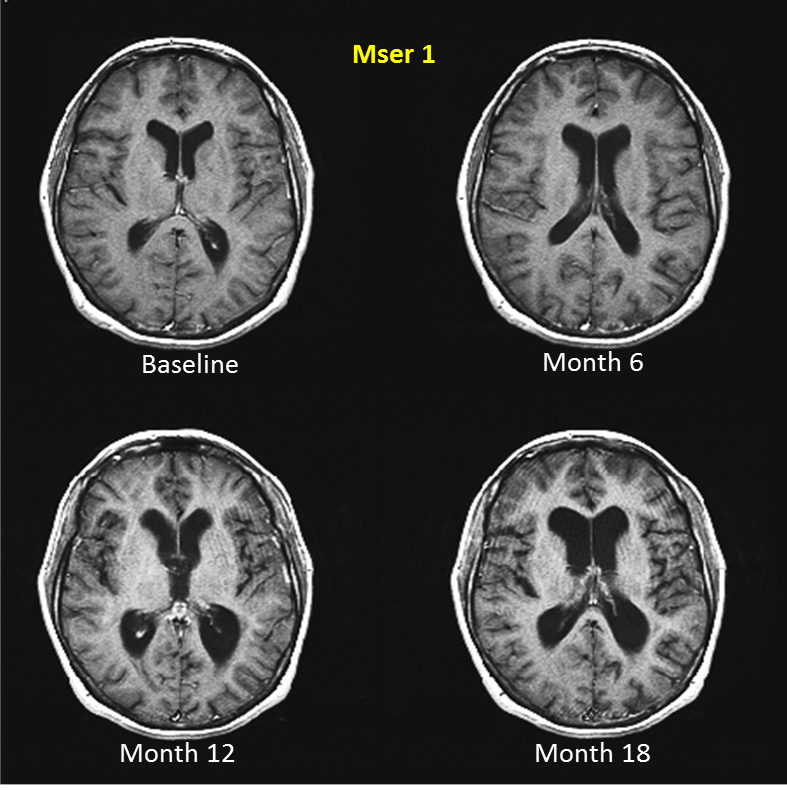

Using MRI scans to reveal early signs of dementia | Health-RI